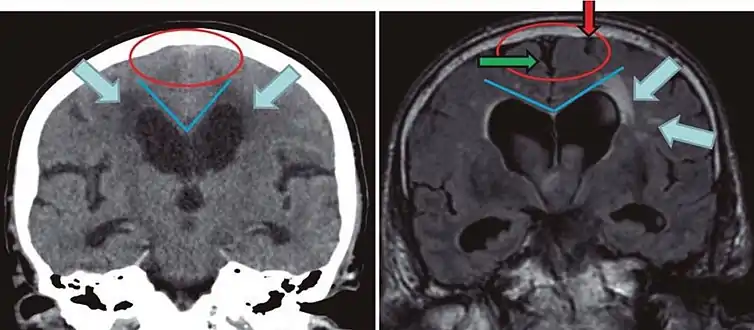

Typical imaging findings in normal pressure hydrocephalus versus brain atrophy.[21]

Normal pressure hydrocephalusBrain atrophy

Preferable projectionCoronal plane at the level of the posterior commissure of the brain.

Modality in this exampleCTMRI

CSF spaces over the convexity near the vertex (red ellipse )Narrowed convexity ("tight convexity") as well as medial cisternsWidened vertex (red arrow) and medial cisterns (green arrow)

Callosal angle (blue V)Acute angleObtuse angle

Most likely cause of leucoaraiosis (periventricular signal alterations, blue arrows ) Transependymal cerebrospinal fluid diapedesis Vascular encephalopathy, in this case suggested by unilateral occurrence